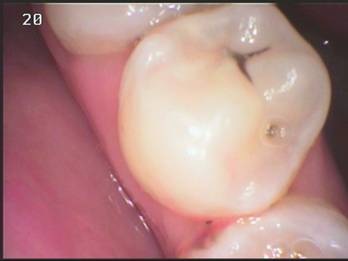

| Ø 小的蛀牙不補,將來就是大的蛀洞。有哪個人的牙齒一長出來就蛀個大洞的呢?但蛀牙剛形成時「不痛也不癢」,我們怎麼知道自己有蛀牙應該要補?當然是要定期到牙醫診所檢查,才是最省事省時的明確之舉啊! 什麼是齒頸部蛀牙? A. 齒頸部蛀牙好發於中年以後,原因並不明確,但建議若有因刷牙不當造成齒頸部磨損最好儘早處理,避免因琺瑯質破壞,增加齒頸部蛀牙的機會。以下患者因蛀牙深入牙齦下方,所以補牙前要先以電刀去除部分牙齦再行處理蛀牙。但因太晚處理,除去蛀牙後發現牙髓露出須進行根管治療 什麼叫預防性充填? A. 現今牙科觀念特別強調『預防重於治療』,所以在兒童牙科治療上除了『定期檢查及塗氟』外,更積極推動『預防性充填』的重要性。所謂『預防性充填』,就是針對乳臼齒及恆牙臼齒,因為我們認為平滑面不易卡髒東西,但有些孩子的乳臼齒及恆牙臼齒表面的溝紋太複雜了,不易清洗,為避免蛀牙發生所以以溝裂充填劑先將溝紋填平,避免將來更進一步蛀牙的發生。當然沒有一件事是一勞永逸的,所以即便做了『預防性充填』,還是要定時檢查,定時更新。 | |